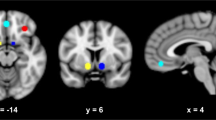

The resting-state seed-based correlation analysis revealed a significant group effect in connectivity at follow-up for bilateral posterior insula (PI) seeds (Fig. 3, N = 18 rTMS, N = 21 sham, per-voxel P < 0.002, cluster corrected at α = 0.05). Both groups revealed a positive correlation between right PI and left precuneus; however, the correlation was significantly lower in the rTMS group [Fig. 3b, rTMS < sham, MNI = 1, −23, 31, cluster size = 8, F(1,36) = 22.88, P < 0.001 η2p = 0.4]. Correlation between left PI and right cingulate was significantly different between groups with positive correlations scores in the rTMS group and negative for the sham group [N = 18 rTMS > N = 20 sham, MNI −11, −71, 28, cluster size 8, F(1, 36) = 15.88, P < 0.001, η2p = 0.3] (Fig. 3b). β Correlation coefficients scores in the rTMS treatment group were not affected by insular depth (Ps > 0.1).

Resting-state connectivity analysis at follow-up. a Insula seed locations identified by maximizing the bilateral connectivity of each seed location. b Brain regions showing significantly different correlation scores in rTMS and sham groups between right PI seed regions and left precuneus and left PI seed and right posterior cingulate (per-voxel P < 0.002, cluster corrected at α = 0.05). The rTMS group presented a significantly lower connectivity between left PI and left precuneus [rTMS < sham, MNI = 1, −23, 31, cluster size = 8, F(1, 36) = 22.88, P < 0.001 η2p = 0.384] and a significantly greater connectivity between left PI and right cingulate [N = 18 rTMS > N = 20 sham, MNI −11, −71, 28, cluster size 8, F(1, 36) = 15.88, P < 0.001 η2p = 0.3]